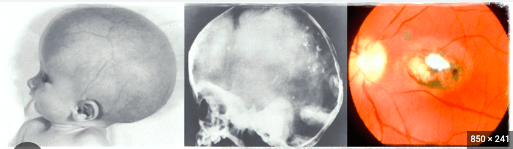

What is this diagnosis of a premature baby? [1]

Interventricular haemorrhage

If a baby suffers from these symptoms, they are most likely to be suffering from:

Toxoplama gondii

Intracranial calcification

Hydrocephalus

Chorioretinitis